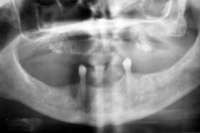

Under the sextant approach, one quadrant is treated and the patient is left to heal for 2 months before proceeding to any additional quadrants. While the patient heals, a 10-day course of antibiotics and 2 months of twice-daily chlorhexidine rinsing may be prescribed. Figure 4 shows a patient who was taking oral bisphosphonates for 3 years and was treated with the sextant approach. As seen in the radiograph, the patient has one molar in the lower right quadrant. This tooth was extracted and the patient was given 2 months to heal (Figure 5 and Figure 6).The patient was placed on antibiotics and chlorhexidine rinse. After 2 months, no signs of BRONJ were observed, and the anterior teeth were scheduled for extraction. They were extracted as atraumatically as possible, and the site was sutured (Figure 7 and Figure 8).The patient then was given another 2 months to heal, following the previous protocol.After 2 months of healing, no BRONJ was observed (Figure 9).

Figure 4 Radiograph of oral bisphosphonate user. Figure 5 and Figure 6 After 2 months of healing, the lower right quadrant showed no signs of BRONJ and the anterior teeth were scheduled for extraction. Figure 6